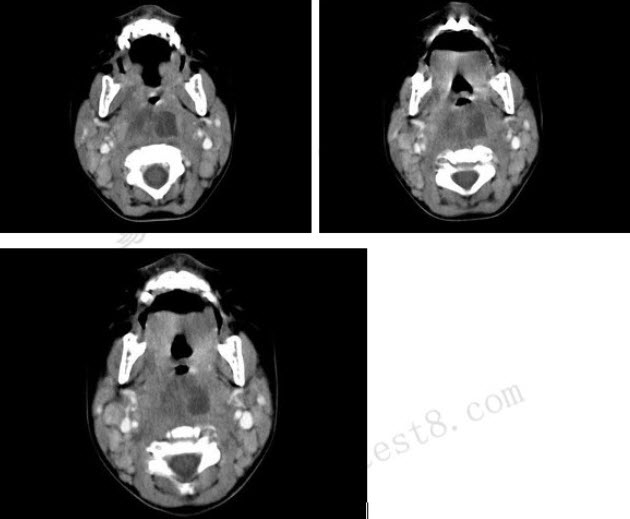

10个月大的婴儿,发热,曾患中耳炎,CT扫描如图所示,正确的描述或诊断是()

A . 咽后壁软组织肿胀

B . 其内密度不均

C . 颈椎骨质未见明显异常

D . 咽后壁脓肿

E . 咽后壁寒性脓肿